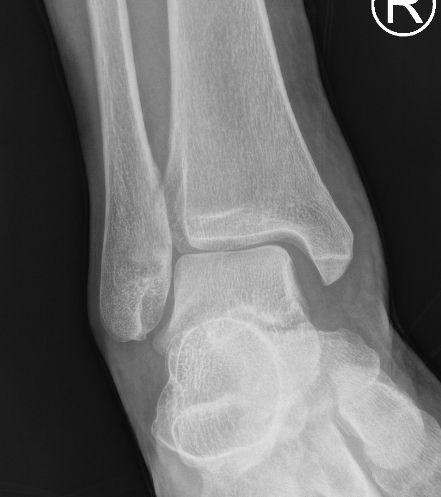

四級踝關節扭傷屬於嚴重病例,前距腓韌帶嚴重撕裂、跟腓韌帶嚴重撕裂及後距腓韌帶嚴重撕裂,踝關節半脫位。症狀包括劇烈疼痛、腫脹、踝關節不穩定和行走困難。

可到 如何自診足踝扭傷 (拗柴) 進行測試

距骨移位 |

「手法復位」後,需用石膏固定3週,並進行X光檢查以確保沒有半脫臼。之後,受傷的踝關節可繼續以石膏固定大約3週,靜止休養,促進癒合。隨後使用短身步行靴(A16)進行大約3週的復健治療,所有治療期間需使用拐杖,避免足踝負重所導致的疼痛及半脫臼,並在拐杖的輔助下進行階段性康復,漸進式負重。